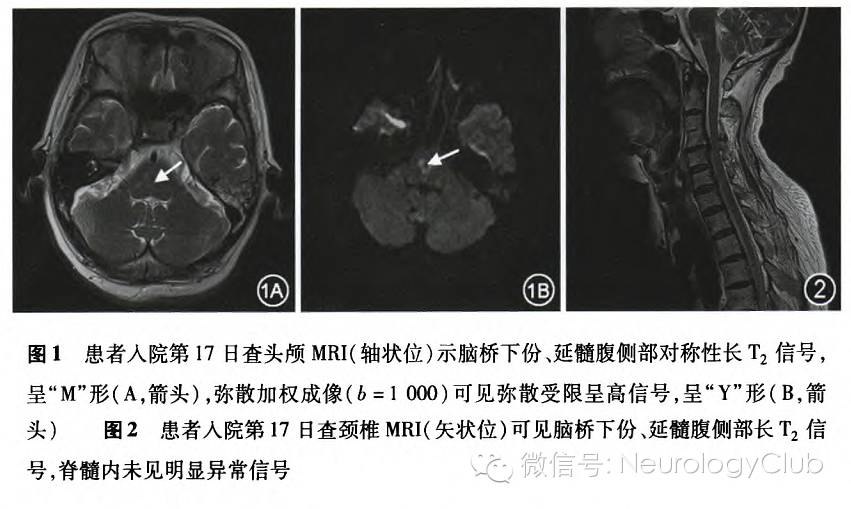

患者女性,60岁,因“头晕、复视、四肢麻木7d,四肢无力、吞咽困难5d”于2014年1月12日入院。患者于1月5日出现头晕、复视、四肢麻木,伴恶心、呕吐。1月6日外院查头CT正常;头MRI及MRA示左侧基底节区软化灶,双侧后交通动脉未显示;四肢肌电图示周围神经损害。1月7日出现四肢无力,不能站立、行走,伴吞咽困难、饮水呛咳、声音低弱、排尿困难。高血压病史5年,血压控制可。有糖皮质激素过敏史。体检:血压130/80mmHg(1mmHg=0.133kPa),意识清楚,双眼内收、外展不能,垂直运动可,右眼闭合无力(露巩膜),吞咽困难,饮水呛咳,构音障碍,咽反射消失,伸舌困难。双上肢(近端及远端)肌力Ⅲ级,双下肢肌力0级,四肢肌张力降低,双上肢腱反射(+),双下肢腱反射消失,双侧Pussep征、巴宾斯基征阳性。辅助检查:脑脊液压力130mmH2O(1mmH2O=0.0098kPa),白细胞计数3×10^6/L,蛋白974mg/L。余常规化验、感染免疫指标均正常。静脉注射免疫球蛋白(IVIG)5d后,病情无好转。1月18日血浆置换后出现过敏。1月29日出现轻度呼吸困难,头MRI示脑桥下份、延髓腹侧部长T1长T2信号,FLAIR像呈高信号,弥散加权成像(b=1000)可见弥散受限呈高信号(图1)。脊髓MRI未见明显异常信号(图2)。脑脊液抗神经节苷脂Q1b(GQ1b)抗体阳性。2月11日查四肢肌电图示双侧拇对掌肌、右侧胫骨前肌呈神经源性改变,双胫神经、腓深神经周围运动传导速度减慢,双胫神经H反射未引出;运动诱发电位示四肢皮质至根段传导延迟,右上肢脊髓刺激周围段传导延迟;体感诱发电位示四肢深感觉传导潜伏期延长,波形分化不良,波幅减低。对症治疗24d后,构音障碍好转出院。10个月后电话随访,患者可进食,但不能行走。

该患者为老年女性,急性起病,2d即达高峰,表现为四肢迟缓性瘫痪、双眼水平运动障碍、右侧面瘫、延髓功能障碍,但意识清楚,是不完全LIS的表现,即除眼球垂直运动外,还保留其他神经功能,如微弱的四肢运动、表情肌运动,哭泣或低声呻吟、哼声等。脑脊液的蛋白-细胞分离和肌电图的神经源性损害可确诊GBS,但与既往报道不同,该患者头颅MRI显示脑干病变,且临床表现符合GBS合并BBE的诊断标准:(1)眼外肌麻痹;(2)意识障碍或锥体束征;(3)四肢肌力≤Ⅲ级。此外,脑脊液抗GQIb抗体阳性也支持BBE的诊断。与既往报道的BBE不同,该患者无明显意识障碍,但脑电图未查。